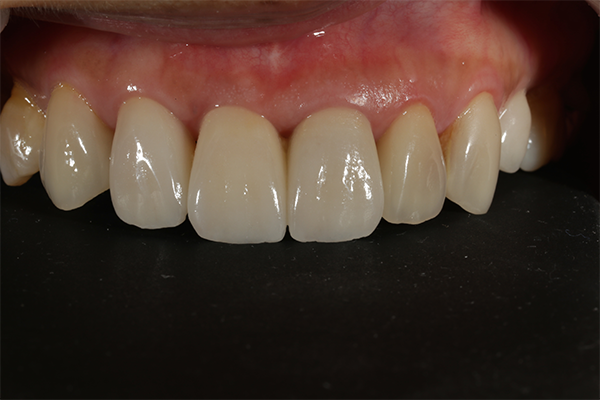

前歯部をオールセラミックによる審美的、機能的な回復をはかったケースです。

前歯ということで歯ぐきのラインにも気をつけより自然な仕上がりにしました。